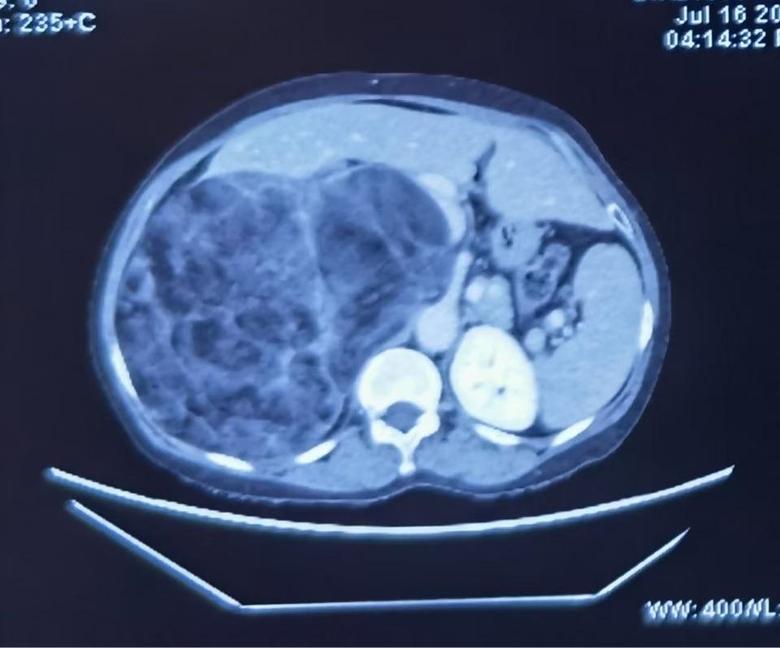

病例1

今日下午,2例巨大腹膜后肿瘤手术在我科顺利开展,腹膜后肿瘤发病率低,手术难度大,手术风险大,国内开展相关手术单位为数不多,我院腹膜后肿瘤手术量连续数年位居国内前列,在腹膜后肿瘤领域团队具有丰富经验,巨大腹膜后肿瘤手术开展,表明该类手术在我院已经成为常态。并且将继续保持国内在领先水平。